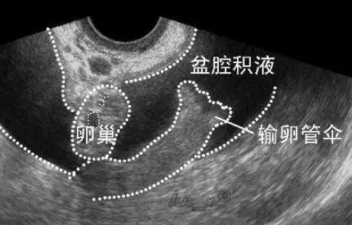

盆腔積液即盆腔積水,大多都是因為婦科的炎癥引起的,盆腔積液是盆腔存在炎性滲出物。盆腔積液可以說是一種表現而不是一種疾病,盆腔積液反反復復如何護理呢?

女性的盆腔是一個流動的循環系統體,腹膜在不斷分泌液體,又在不斷地回吸收液體,所以盆腔里有少量的積液也是正常的,稱生理性盆腔積液,勿需太過緊張。但中度以上腹水時就可能是病理性的積液,需要注意。

在臨床上大多數婦女的盆腔積液是由于炎癥引起,是盆腔存在炎性滲出物。其他還有卵巢腫瘤、子宮內膜異位癥、結核、宮外孕、囊腫的破裂、黃體破裂等這些情況可以引起病理性的積液。